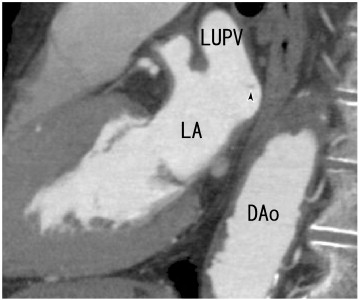

64-MDCT sagittal images showed thrombi in the LA (arrowhead). DAo: descending ...

Fig. 4.

64-MDCT sagittal images showed thrombi in the LA (arrowhead). DAo: descending aorta, LA: left atrium, and LUPV: left upper pulmonary vein.